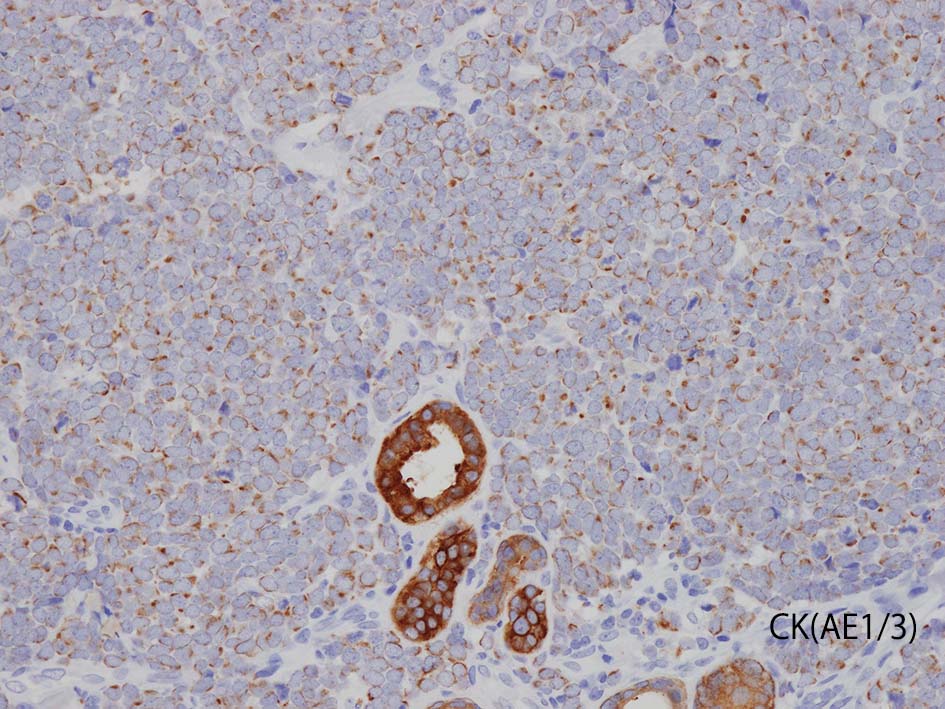

- 陽性上皮系マーカ; CAM5.2, AE1/3, CK20, BerEP4, EMA

- CK20の染色態度は核周囲にdot状にそまることが特徴的. (MCC[87%]のみではなく肺小細胞癌の4.6%にもこの陽性パターンをみることに注意*2)

CK20

血管を間質にしてround cellsが索状に増殖する所見. rossett様配列がある. CK20は特徴的な dot-like patternを示す. クリックで大きな画像が見られます.

本例では, dot状だけでなく, 細胞周囲にも陽性像が認められる.

CK(AE1/3); CK20は含まない, のほうがdot-likeな染まりをしている. CK20は膜にも陽性になっている. LCAは陰性. 神経内分泌マーカのchromograninA, synaptophysinは陽性.